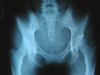

Jun 2 2003: We'll Be Amputating at the Hip Just to Be Sure

After only 3.5 months of delay, the hip has been x-rayed. The latest orthopedic surgeon found no fractures to the pelvis nor is there any apparent damage to the femoral head. He thinks the popping is from an unhappy iliopsoas tendon snapping. Doc said learning to rehab the tendon through physical therapy should help, and if it doesn't improve in six months I should go get an MRI. Being someone who Officially Hates The Medical Insurance System, I found some iliopsoas-related exercises on the internet I can do so I'll skip the PT office visit because The Evil Empire Known As Blue Cross will probably try to stick me for the entire bill. If the hip can't fix itself over time, I'm just gonna have to fall back on Darwinism: The right hip gets weak and frail; the left one attacks and kills it and gets to take over the entire jungle. I have no problems with that.

Yes...if you stare really hard at the xray, you can see the shadow of my Flat Asian Ass.